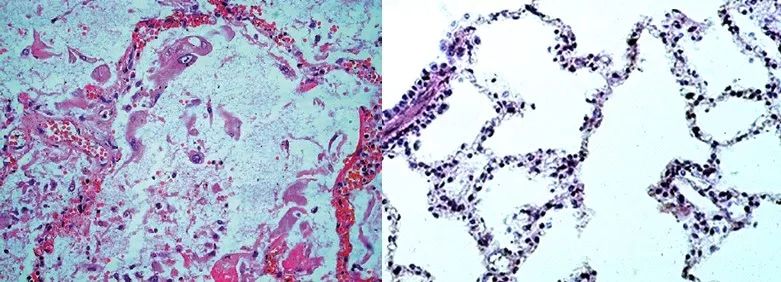

肺组织切片镜下可见弥漫性的肺泡损伤,伴有支气管上皮剥脱,纤毛脱落,鳞状上皮化生等病变;大部分死者肺泡和肺间质巨噬细胞浸润,肺泡上皮细胞增生形成双嗜性胞浆丰富的多核巨细胞,即巨细胞肺炎。大量的渗出以及白细胞的浸润,导致了肺部外观上明显膨隆、增大,重量增加[2]。

(左)SARS肺炎伴部分形成巨细胞的肺泡上皮细胞,肺泡内可见大量纤维素性渗出液,肺泡壁毛细血管淤血,肺泡壁完整性被破坏[3];(右)正常肺泡和肺泡囊|Color Images of Histological Sections

上述以呼吸系统为主的症状,就是病毒对肺部原发性以及继发性损伤导致的。[3]